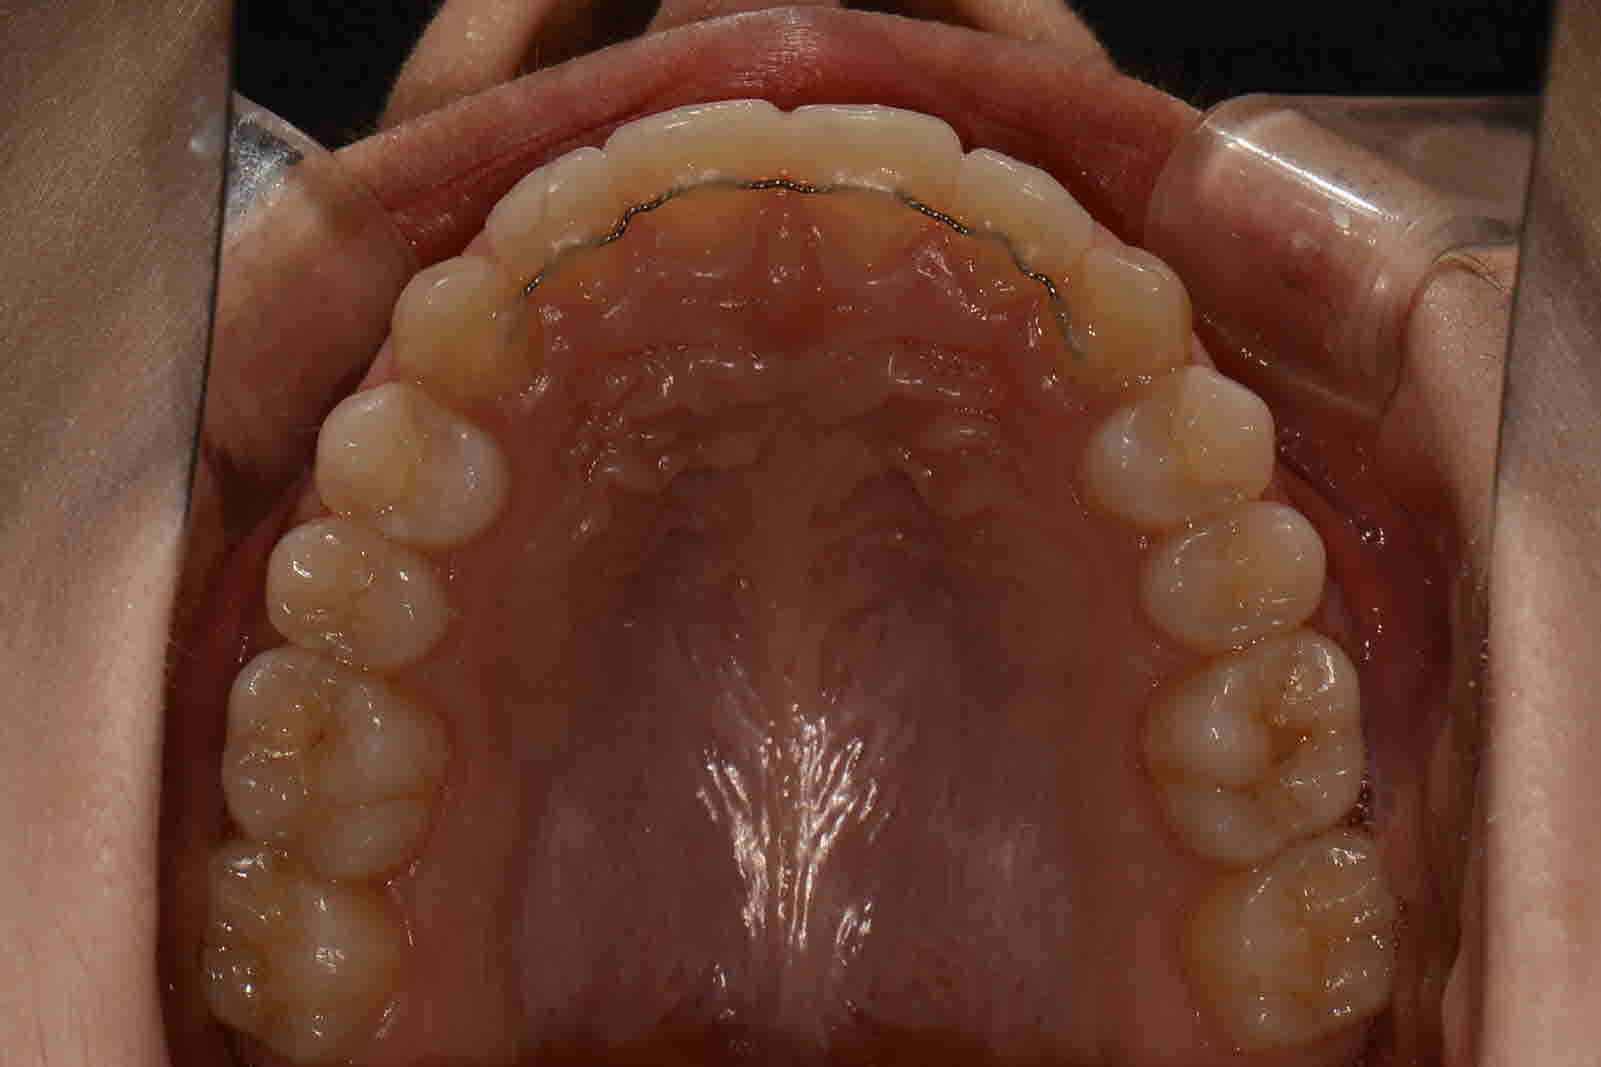

교정시작 교합면

2017년 6월 교합면

2018 년 4월 교합면

교정완료 교합면